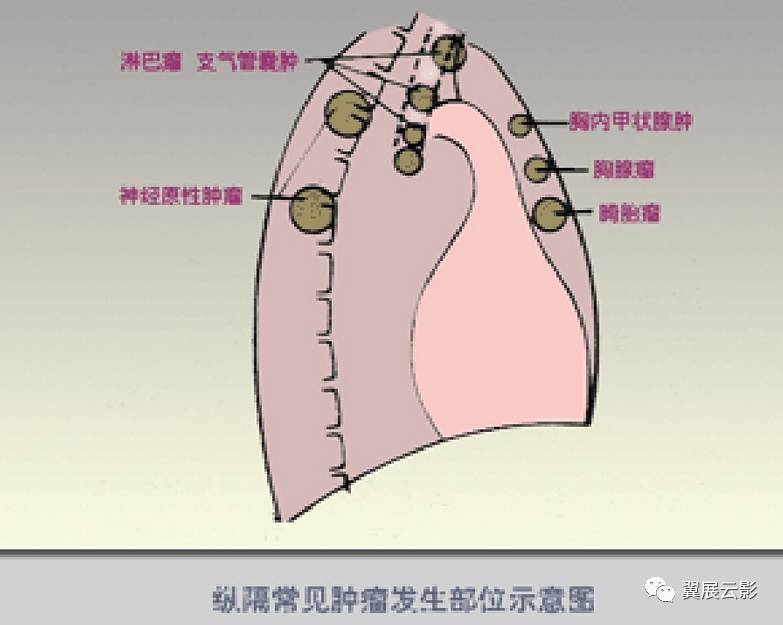

详解纵隔肿瘤以及鉴别诊断

图片尺寸783x625